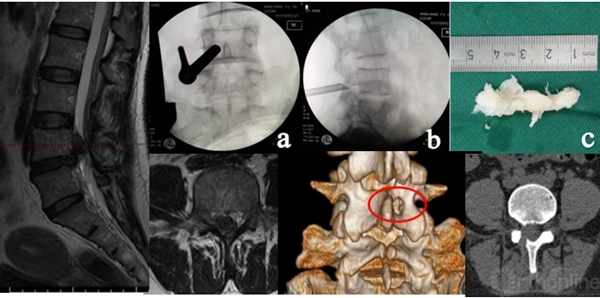

介入诊断技术:选择性神经根阻滞技术、椎间盘造影技术等,不仅可以从患者的主观感受进一步精准诊断,同时对脊柱内镜手术的疗效可以起到预测作用。

怀疑融合临近节段极外侧突出,选择性神经根阻滞术明确诊断

术前造影显示后纵韧带完整性,术中保护后纵韧带

靶向穿刺